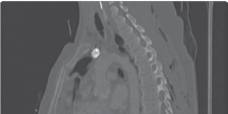

The foundation of successful thoracolumbar surgery lies in exhaustive preoperative planning. Standard imaging protocols must include full-length, free-standing 36-inch orthogonal radiographs to accurately assess global coronal and sagittal balance. The use of EOS low-dose biplanar imaging has become the gold standard, allowing for simultaneous assessment of the spine, pelvis, and lower extremities, which is crucial for identifying compensatory mechanisms such as pelvic retroversion, hip extension, and knee flexion. Magnetic Resonance Imaging (MRI) is mandatory to evaluate the neural elements, assess disc hydration, and identify central, lateral recess, or foraminal stenosis.

High-resolution computed tomography (CT) with multiplanar reconstruction is essential for evaluating bone stock, identifying facet arthropathy, and planning pedicle screw trajectories. In cases of severe deformity or revision surgery, CT-based 3D templating software allows the surgeon to simulate osteotomies, calculate the exact degree of correction required to achieve spinopelvic harmony, and pre-contour rods. The surgeon must meticulously calculate the required Lumbar Lordosis (LL) based on the patient's Pelvic Incidence (PI), plan the upper and lower instrumented vertebrae (UIV and LIV) to avoid ending the construct at the apex of a kyphotic curve, and determine the necessity of pelvic fixation.

Clinical & Radiographic Imaging Archive